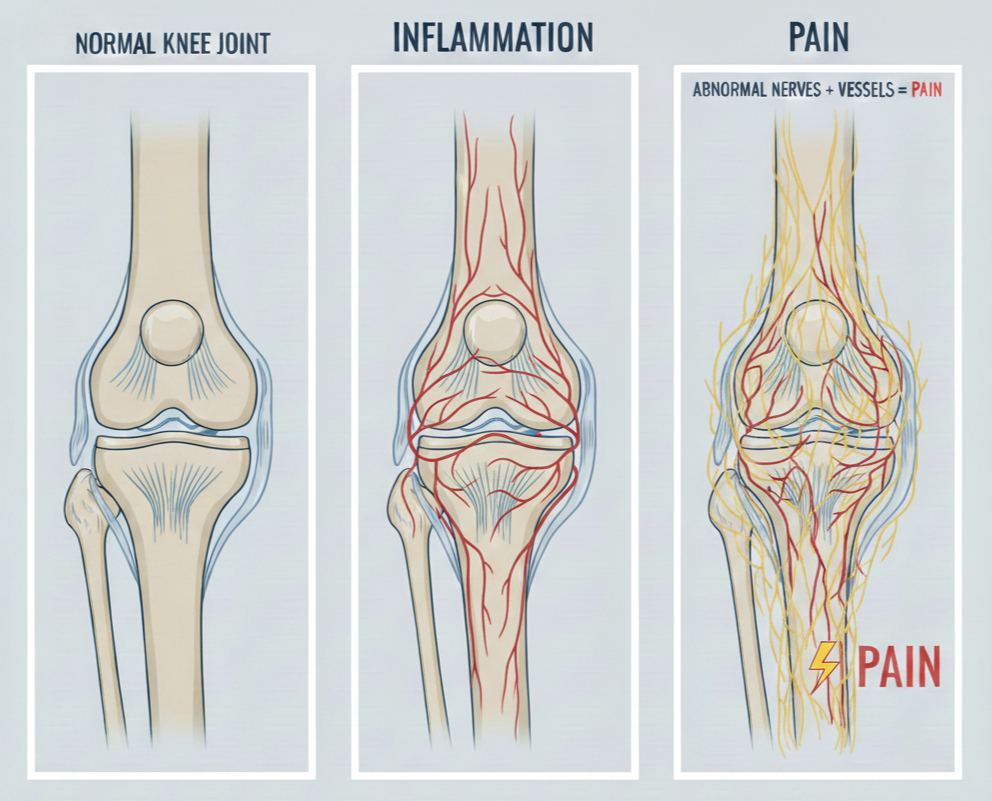

Abnormal Blood Vessels and Nerves: The Source of Pain

When chronically inflamed tissue is examined under the microscope, a consistent finding emerges — clusters of abnormal, newly formed blood vessels called neovessels. Unlike normal blood vessels, which have well-organised walls and regulate blood flow effectively, these neovessels are structurally deficient. Their walls are incomplete and leaky, contributing to ongoing swelling and delivering a continuous supply of inflammatory cells and chemicals to the affected area.

New nerve fibres grow alongside these abnormal blood vessels. These nerves serve no useful purpose. They do not provide normal sensation or protective pain signals. Instead, they are densely packed with pain receptors, fire at lower thresholds than normal nerves, and can even generate pain signals spontaneously. This is why chronic musculoskeletal pain often seems out of proportion to the degree of structural damage visible on imaging.

The combination of abnormal blood vessels feeding inflammation and abnormal nerves generating pain creates the engine that drives chronic musculoskeletal pain.